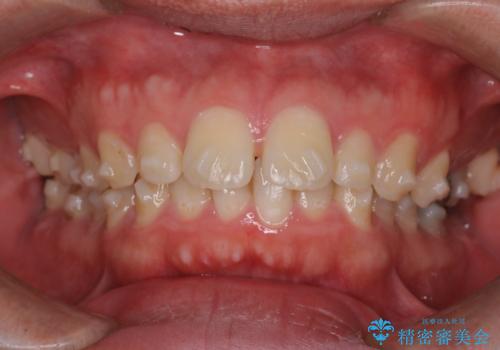

【前突症例】前歯を下げたい

- 前歯の隙間と口元を主訴に来院されました。

インビザラインにて治療を行いきれいな歯並びをつくることができました。